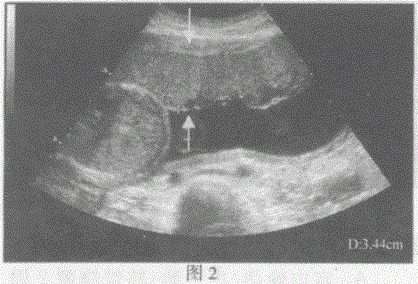

问题 请指出下图箭头间所指的是宫内妊娠哪一部位:

选项 A.图1:胎盘厚度图2:羊水深度 B.图1:羊水深度图2:胎盘厚度 C.图1:胎儿双顶径图2:胎儿腹围 D.图1:胎儿股骨长径图2:胎儿股骨长径

答案 B